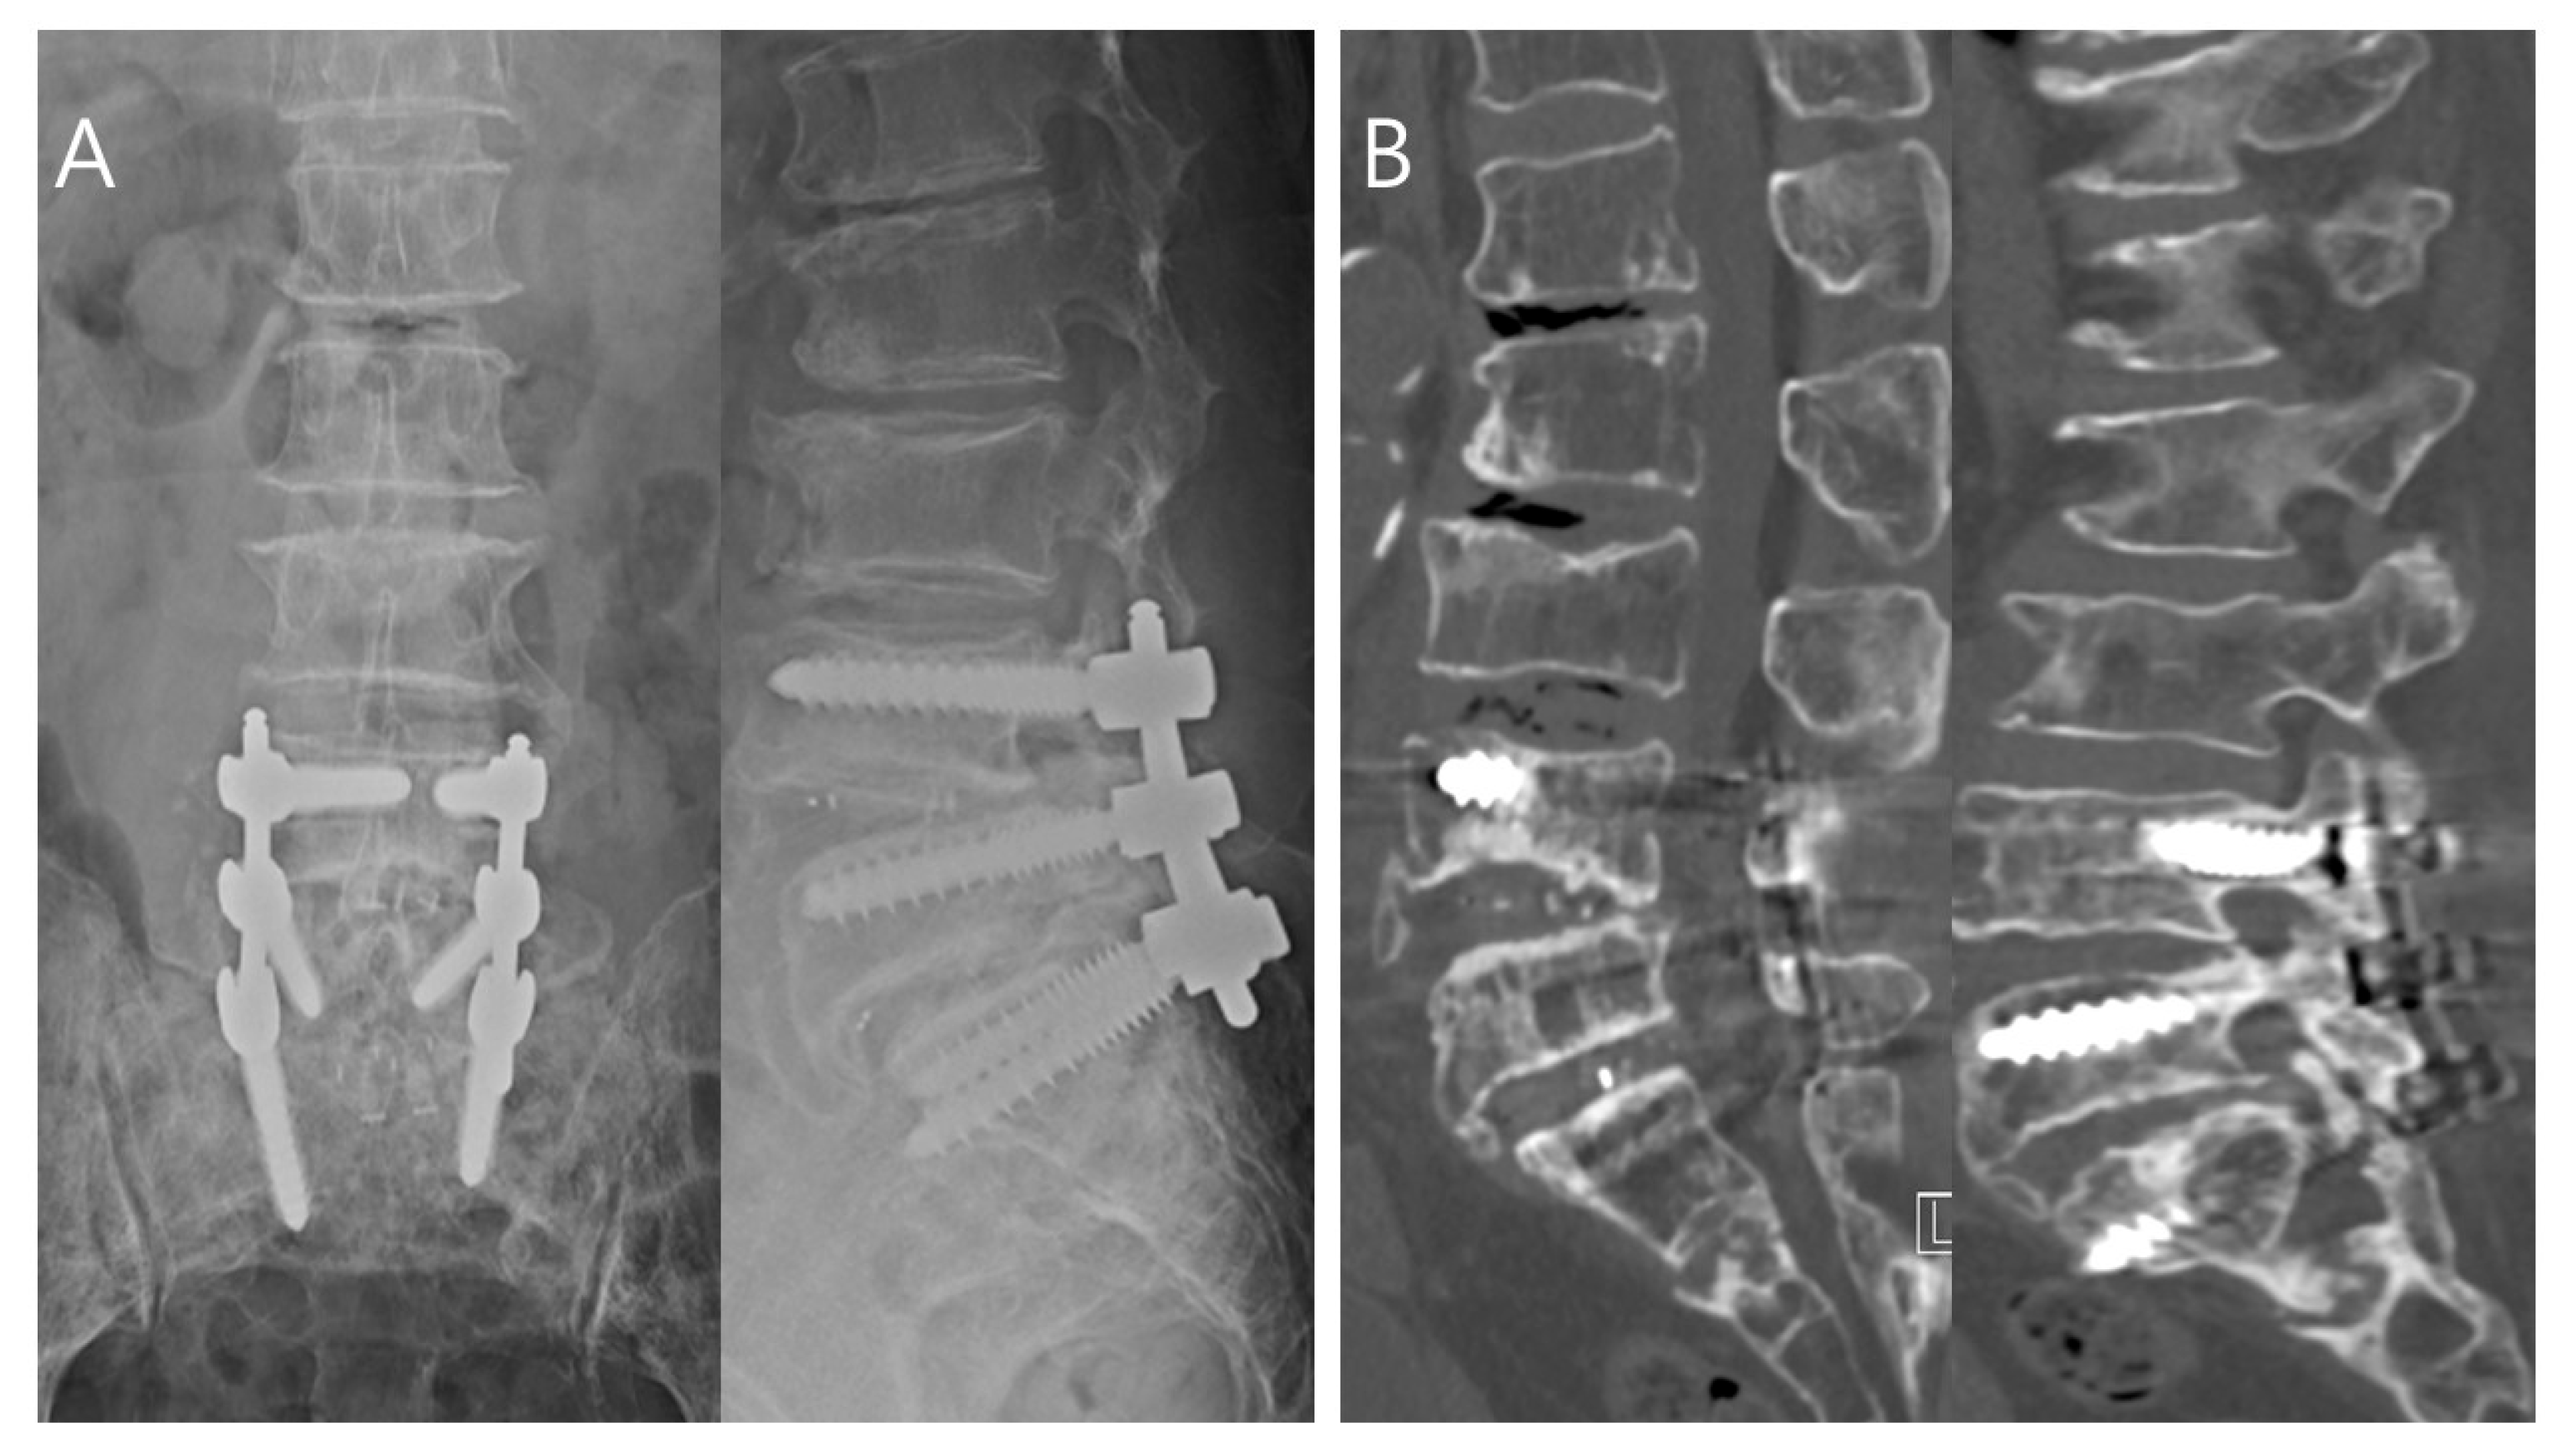

3.2.1. Toothbrush Group Patient: Successful Treatment

3.2.2. No-Toothbrush Group Patient: Treatment Failure